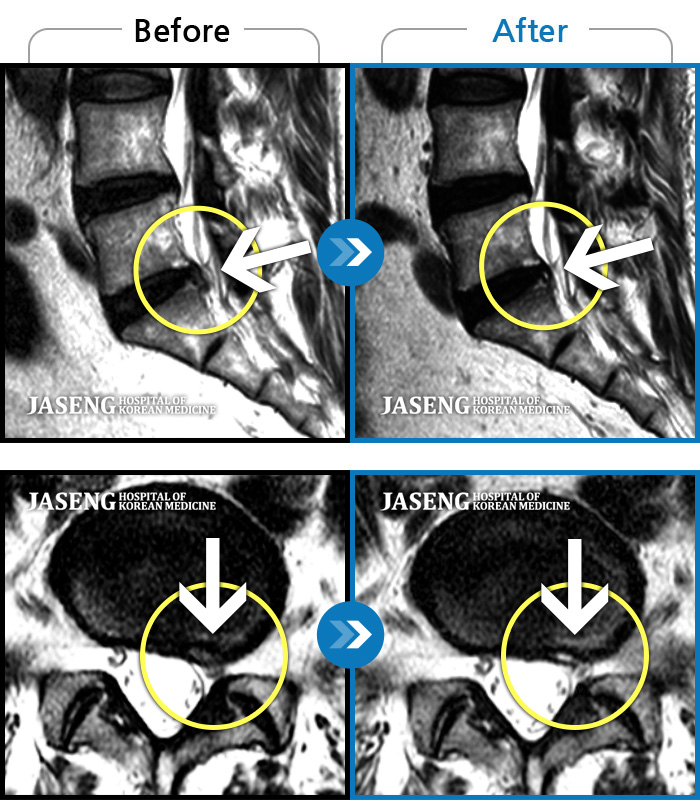

MRI 치료사례

좌측 다리 저림 증상이 너무 심하여 앉거나 서는 것이 안되고 다리를 들어올릴 수 가 없었다.